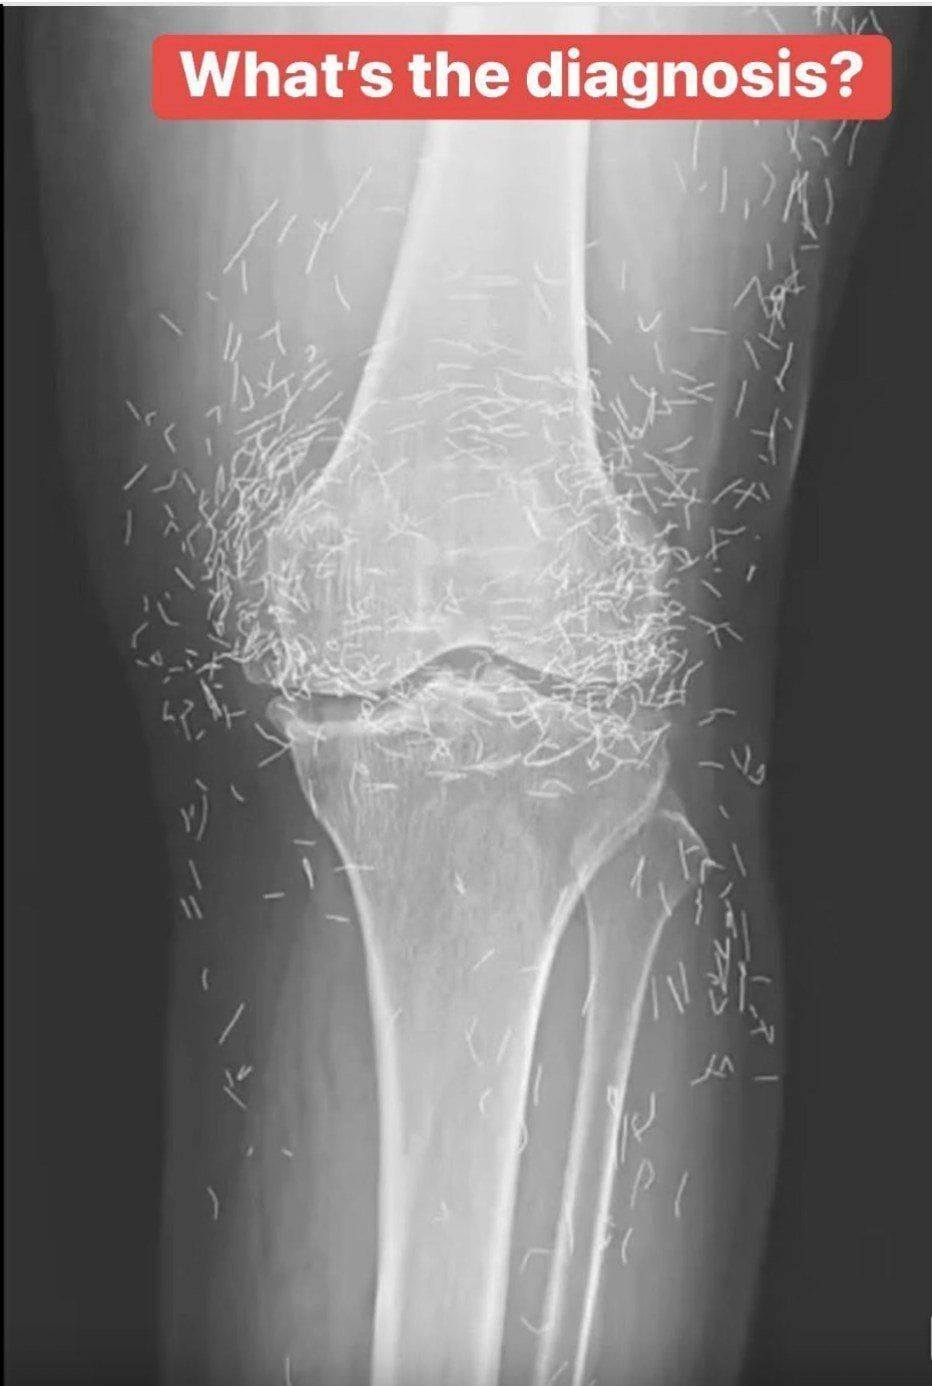

Years later, when doctors took X-rays to evaluate her knee condition, they weren’t prepared for what appeared on the images. Her knees were filled with dozens of bright, metallic flecks — tiny needles embedded deep within the joint area.

The findings were later documented in a case published by the New England Journal of Medicine.